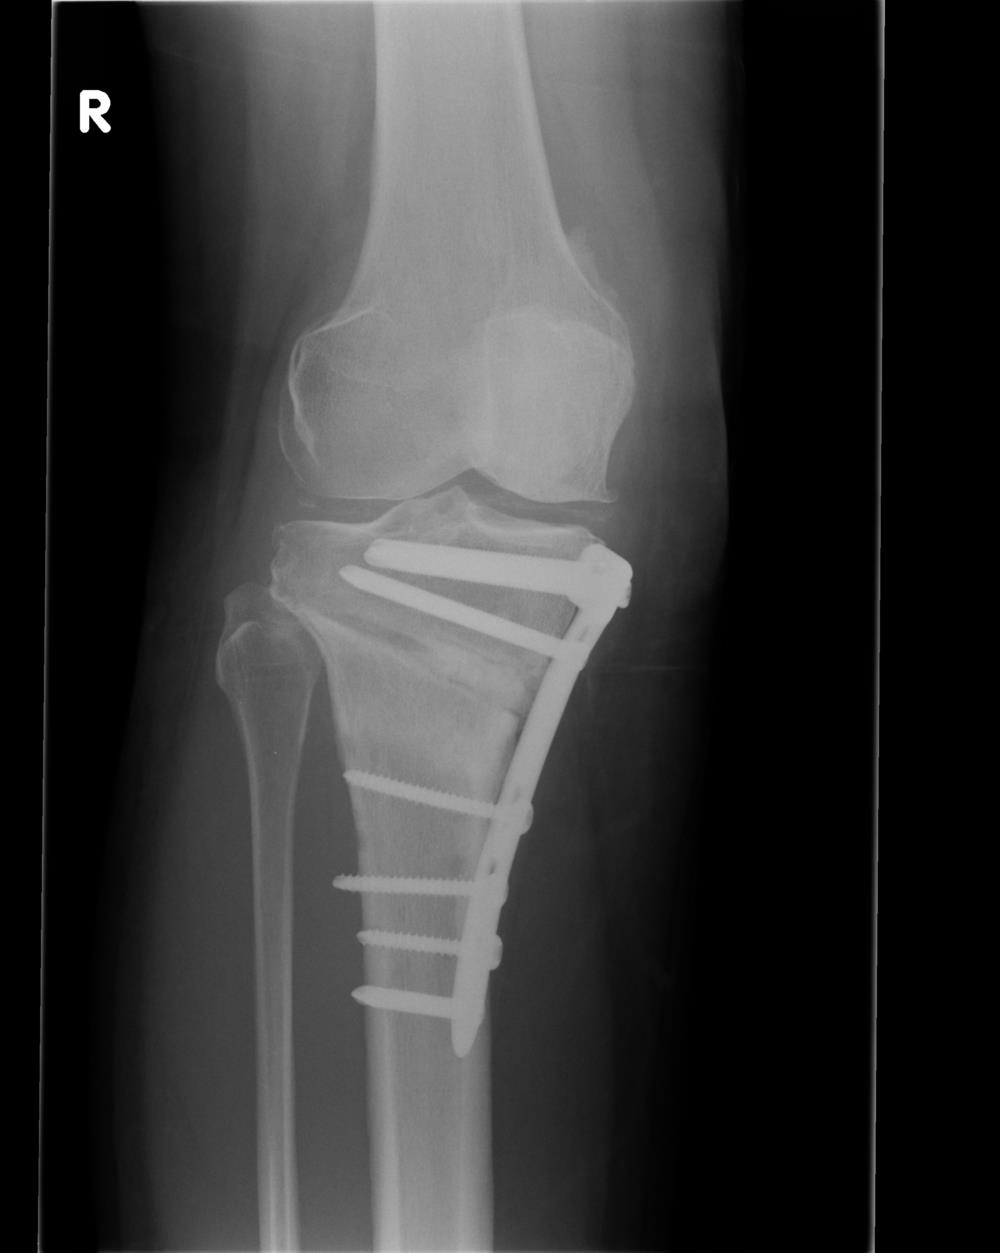

The location of the removed wedge of bone depends on where osteoarthritis has damaged the knee cartilage. The most common type of osteotomy performed on arthritic knees is a high tibial osteotomy, which addresses cartilage damage on the inside (medial) portion of the knee. The procedure usually takes 60 to 90 minutes to perform.

During a high tibial osteotomy, surgeons remove a wedge of bone from the outside of the knee, which causes the leg to bend slightly inward. This resembles the realigning of a bowlegged knee to a knock-kneed position. The patient's weight is transferred to the outside (lateral) portion of the knee, where the cartilage is still healthy.

After regional or general anesthesia is administered, the surgical team sterilizes the leg with antibacterial solution. Surgeons map out the exact size of the bone wedge they will remove, using an X-ray, CT scan, or 3D computer modeling. A four- to five-inch incision is made down the front and outside of the knee, starting below the kneecap and extending below the top of the shinbone.Guide wires are drilled into the top of the shinbone (tibia plateau) from the outside (lateral side) of the knee. The wires usually outline a triangle form in the shinbone.

A standard oscillating saw is run along the guide wires, removing most of the bone wedge from underneath the outside of the knee, below the healthy cartilage. The cartilage surface on the top of the outside (lateral side) of the shinbone is left intact. The top of the shinbone is then lowered on the outside and attached with surgical staples or screws, depending on the size of the wedge that was removed. The layers of tissue in the knee are stitched together, usually with absorbable sutures.